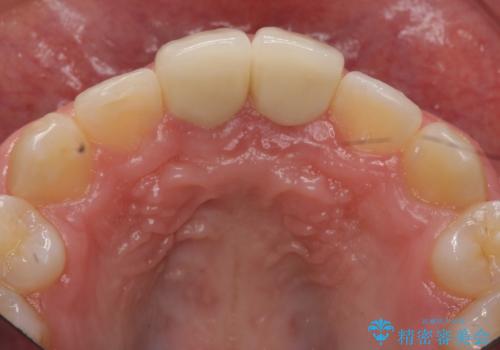

また、プラスチックでつぎはぎになっていたため、虫歯を取りしっかりとしたクラウン(被せもの)としました。

前歯の変色及び、ガタガタもしっかりなおり、満足していただきました。